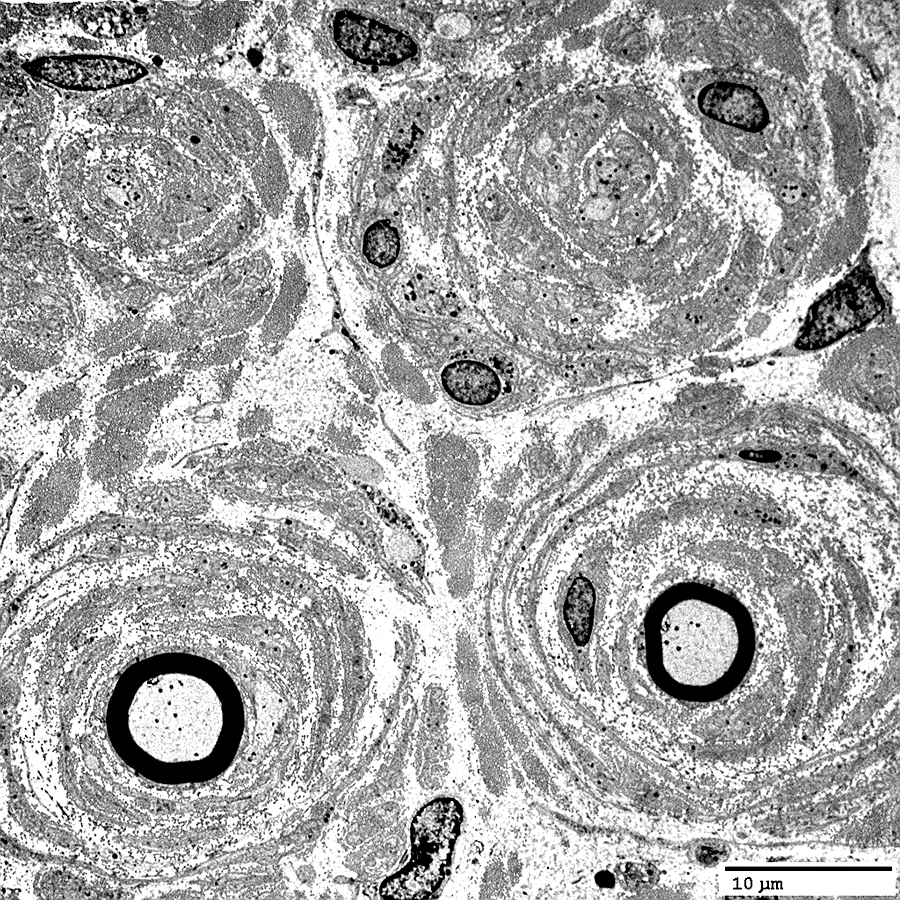

Onion Bulbs: Large, Late

Toluidine blue stains of plastic nerve sections

Onion bulbs, Large

Multiple Connective tissue layers

& Schwann cell processes

around thinly myelinated axons.

Onion bulbs may contain 0, 1,

or several, axons.

Several layers of Basal lamina, Connective tissue & Schwann cell processess around thinly myelinated axons.

Onion Bulbs: Ultrastructure

CIDP, Childhood onset

From: Robert Schmidt MD